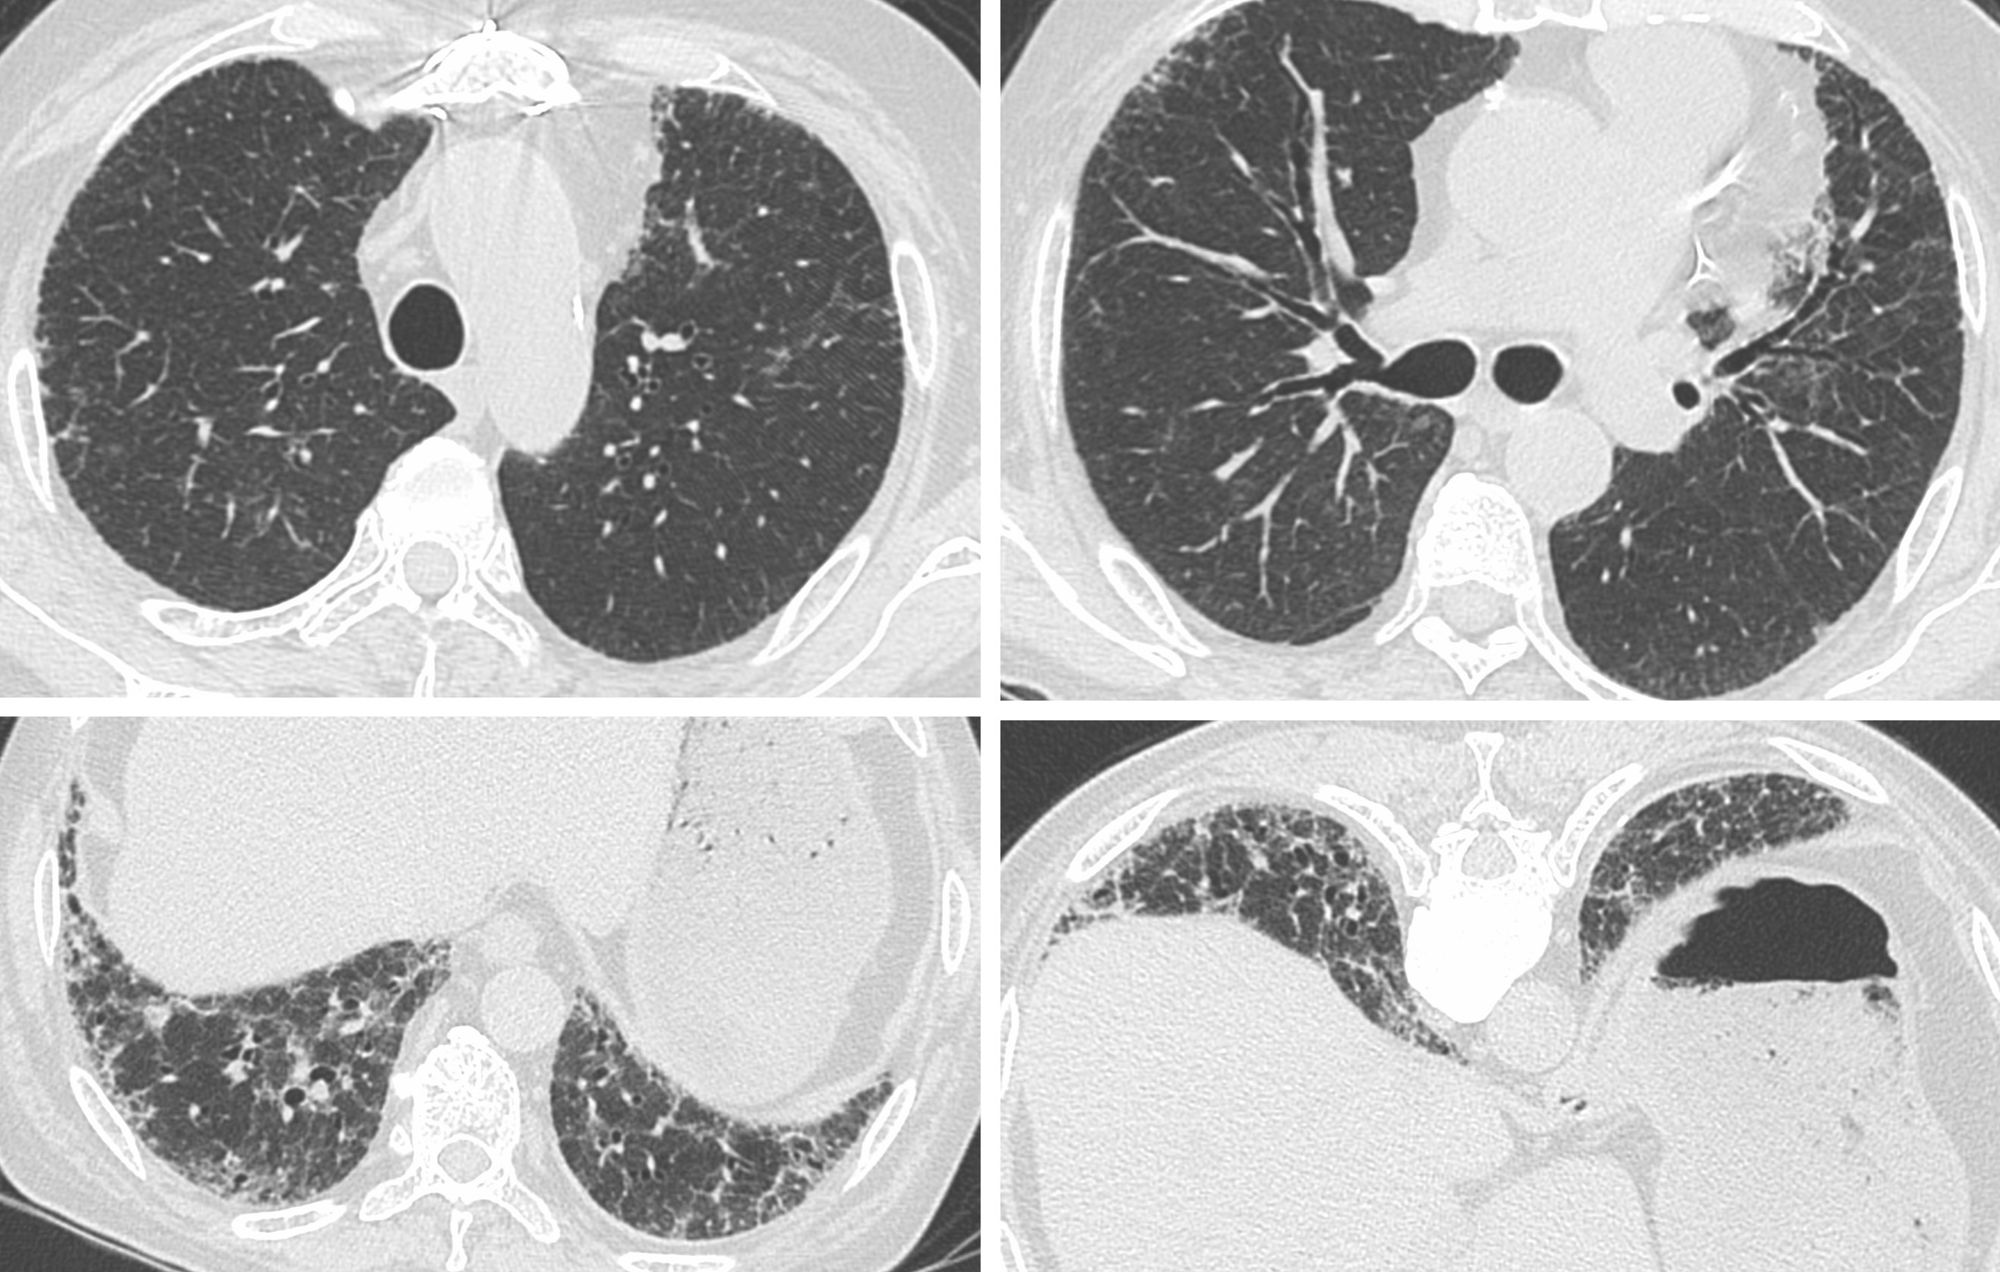

A 67-years old patient presented with gradually progressive breathlessness.

A CT scan was done.

- Probable UIP/IPF

- Typical UIP/IPF

- Fibrotic hypersensitivity pneumonitis

- Interstitial lung abnormality (ILA)